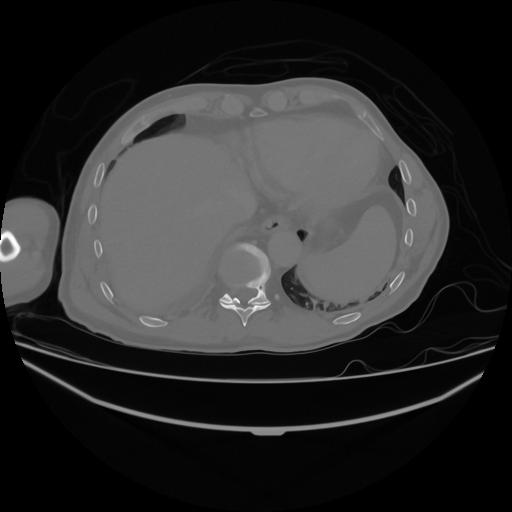

5 CUERPO,CE,Vol,1.0,CUERPO,,